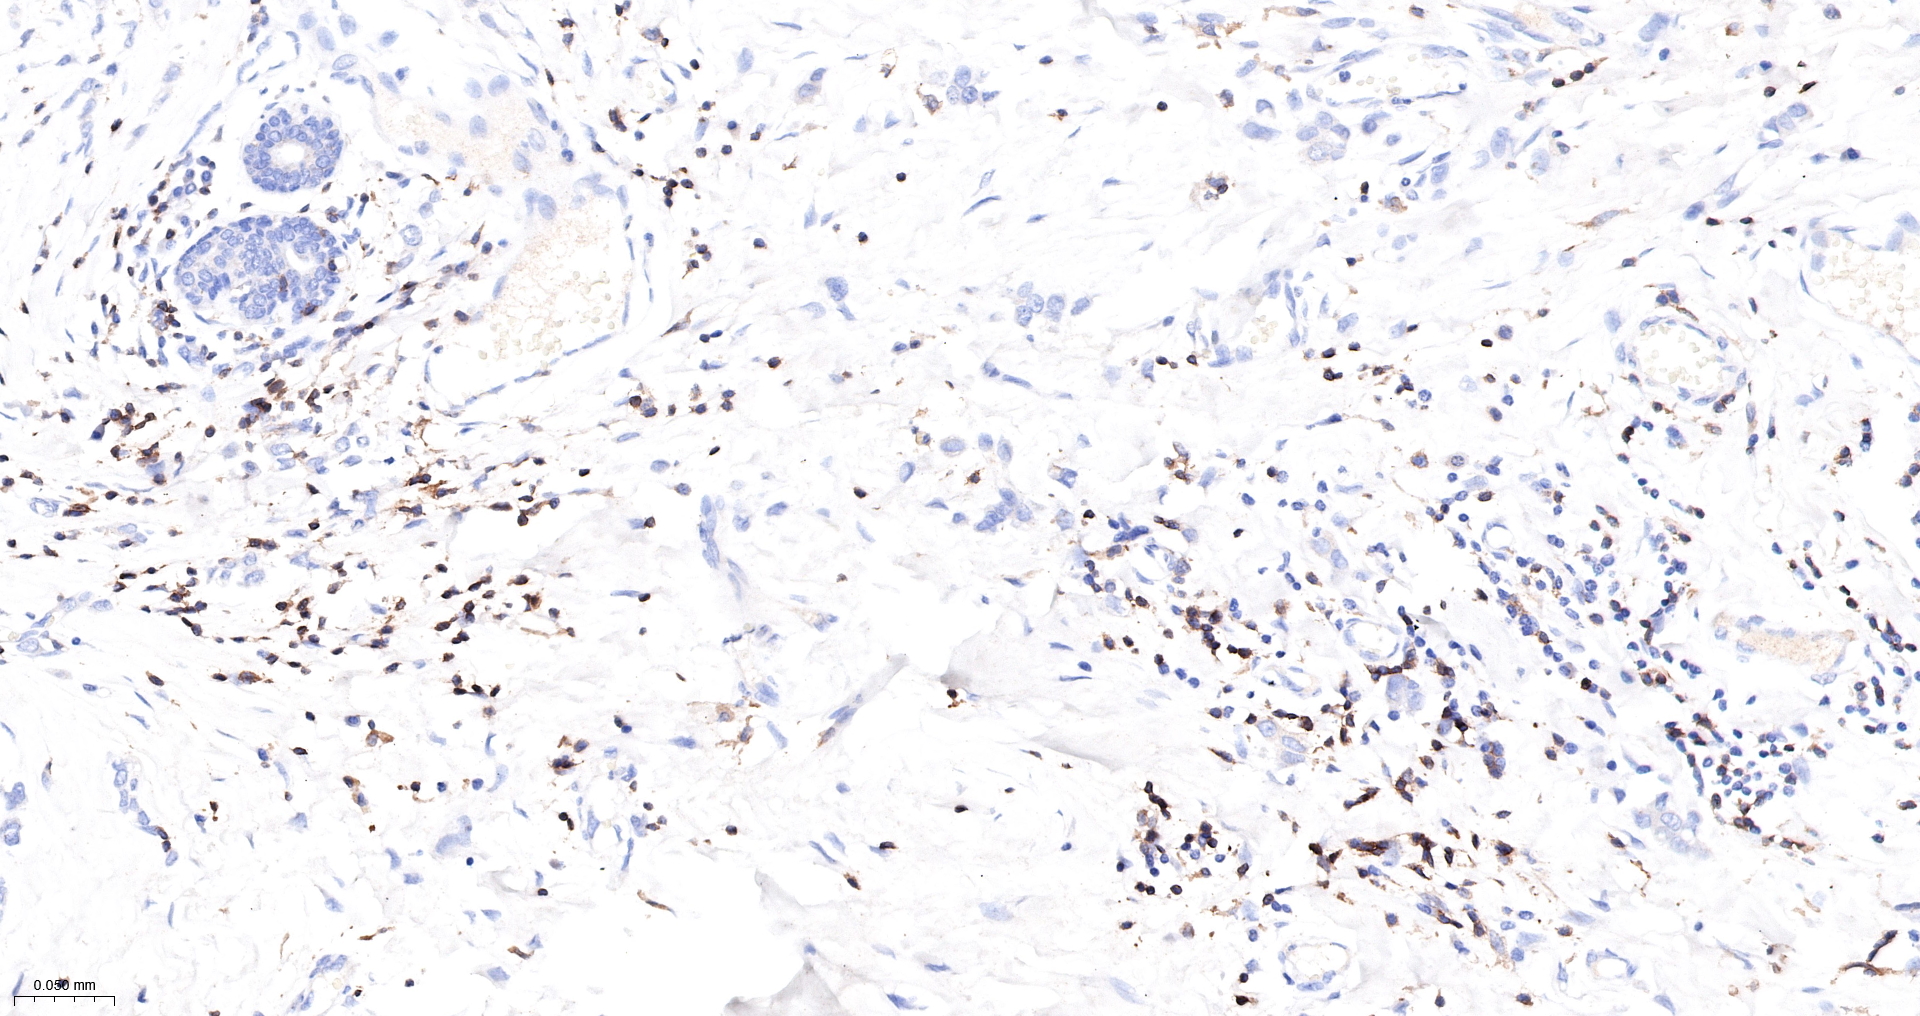

| CD3E Recombinant Antibody |

| WB, IHC-P, IHC-F, IF |

| IHC-P |

1:500-1000 |